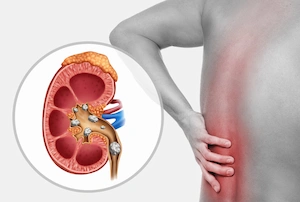

علائم وجود سنگ مثانه ۱۱ میلیمتری که باید جدی بگیرید

بیماران معمولاً با علائم زیر به مرکز ما مراجعه می کنند:

- درد شدید در ناحیه زیر شکم: که ممکن است به لگن یا آلت تناسلی انتشار یابد.

- هماچوری یا وجود خون در ادرار: که به دلیل خراشیدگی دیواره مثانه توسط سنگ ایجاد می شود.

- تکرر ادرار ناگهانی: به خصوص در طول شب.

- قطع و وصل شدن جریان ادرار: وقتی سنگ مانند یک دریچه مسیر خروجی را می بندد.

- سوزش شدید: هنگام دفع ادرار که نشان دهنده تحریک یا عفونت است.